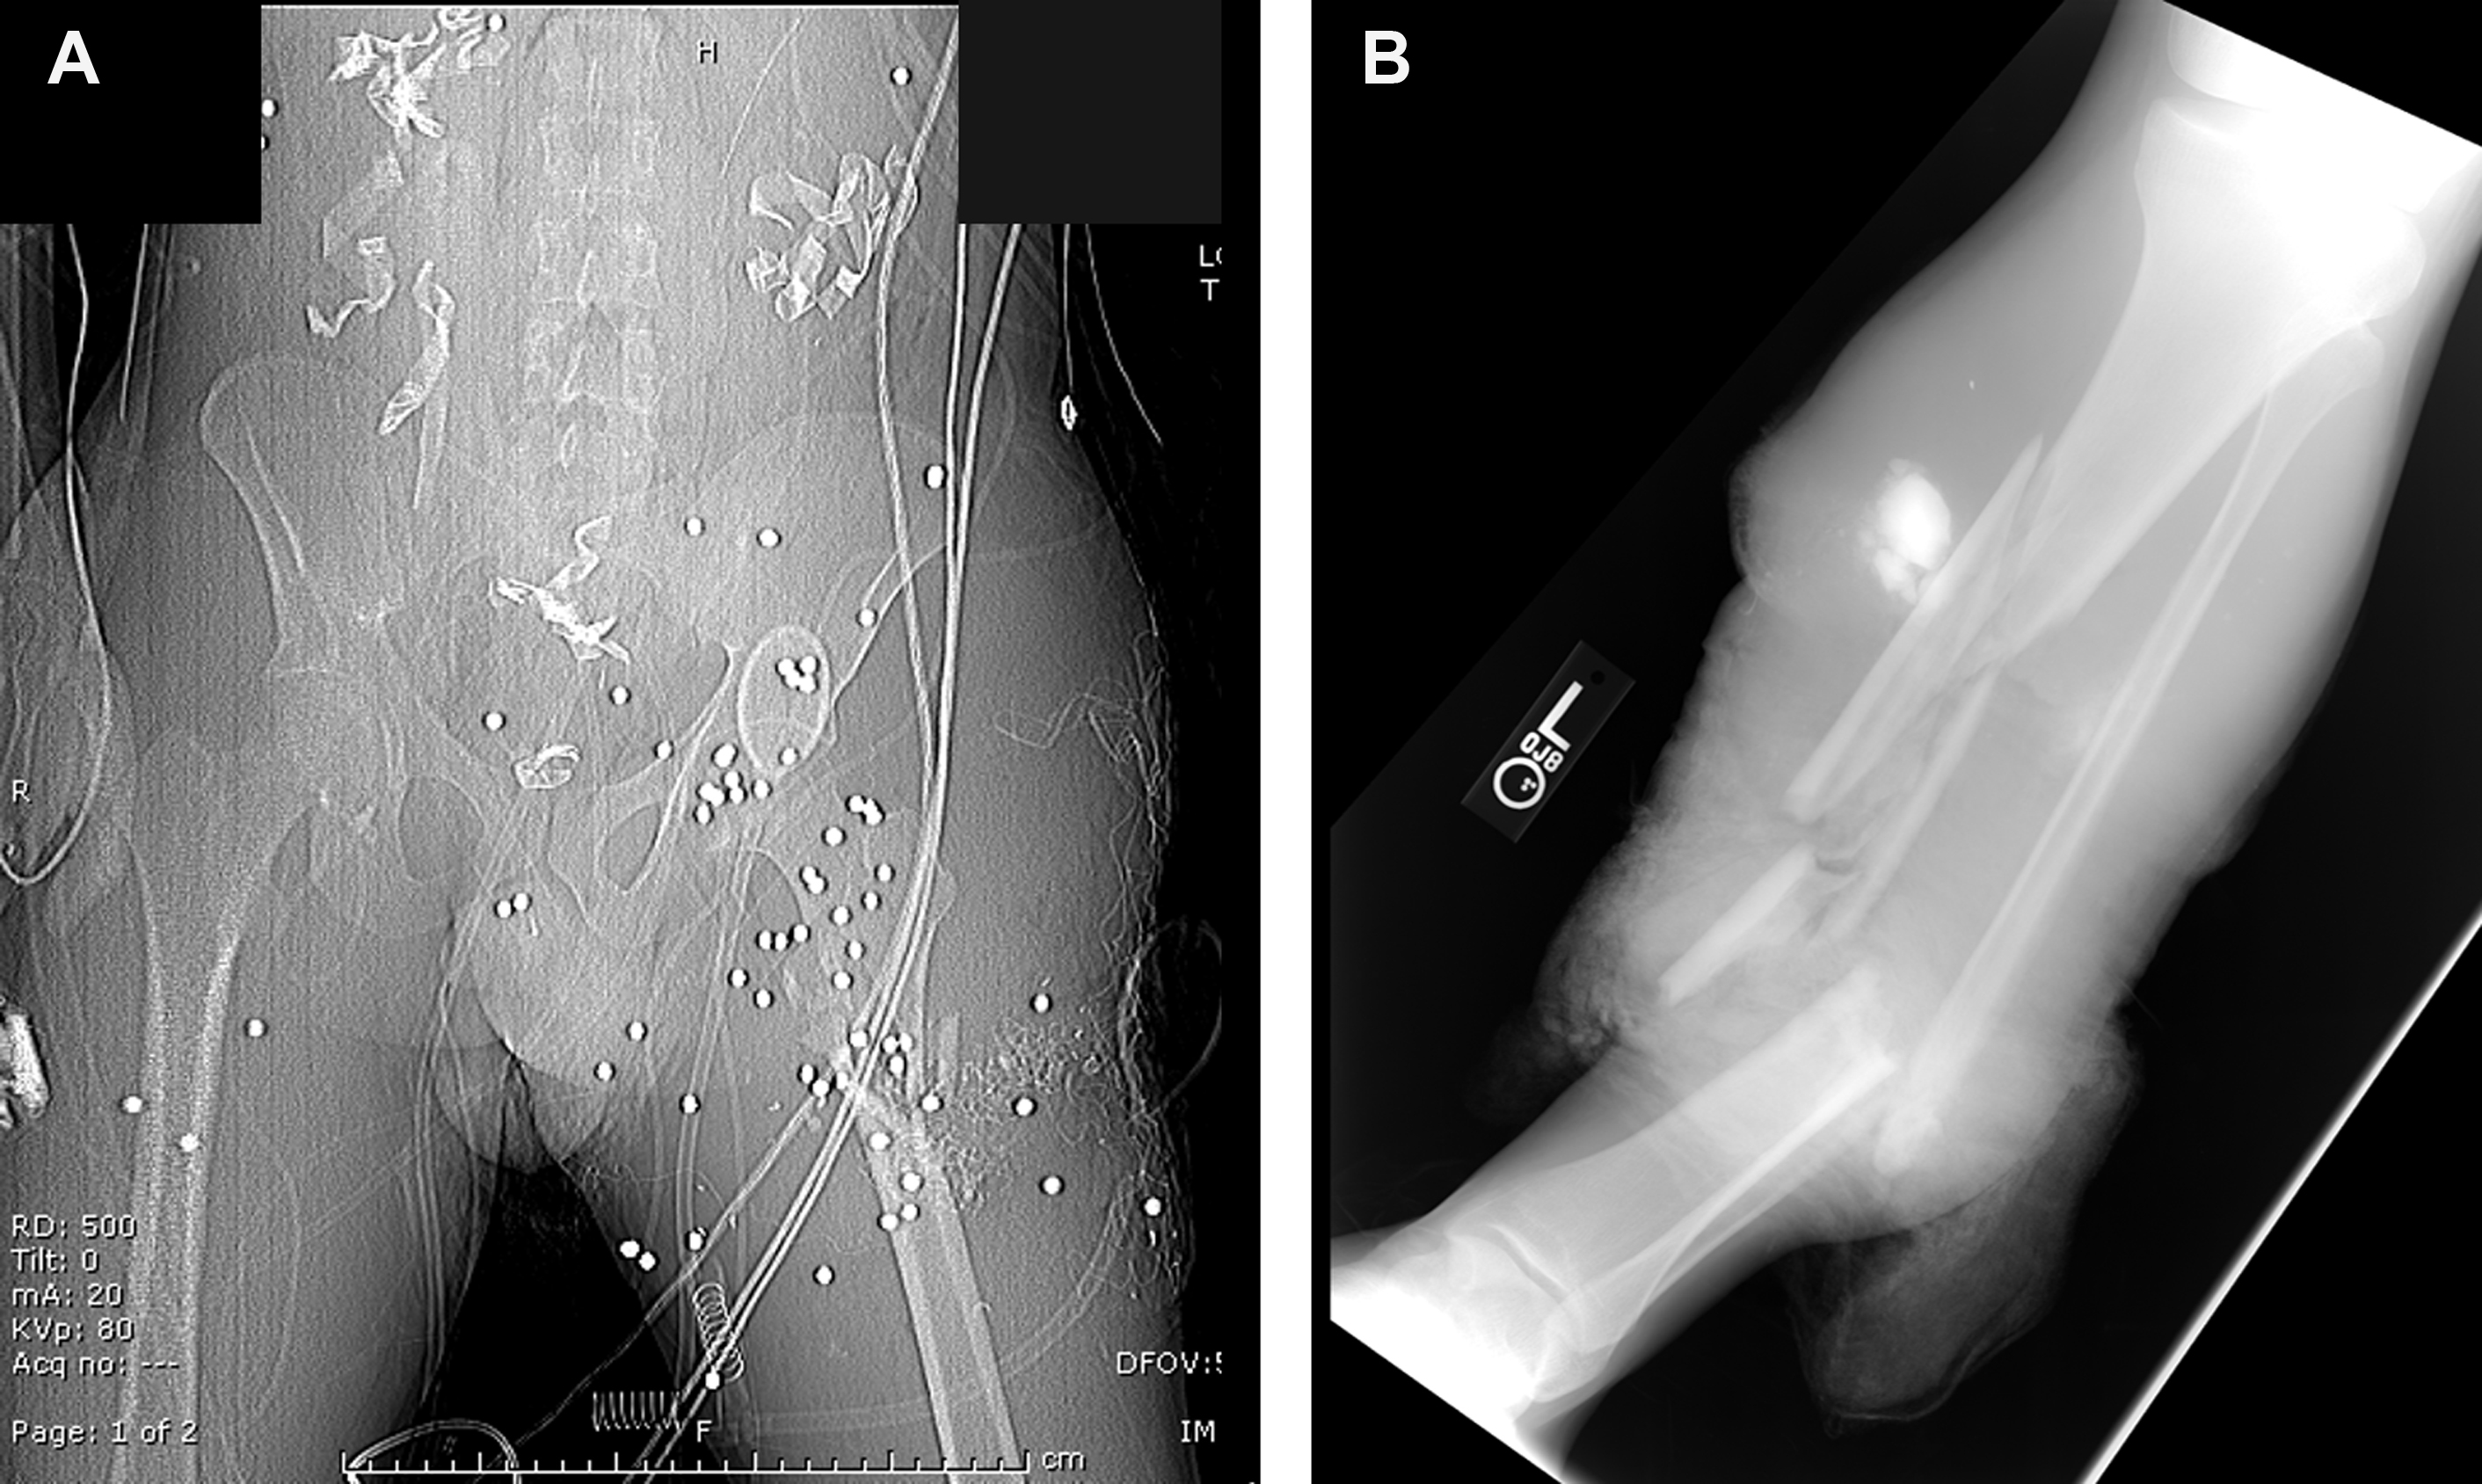

Modern conflict presents extremity reconstructive surgeons with a new set of challenges when treating combat casualties returning from the war theater. The recent conflicts in Iraq and Afghanistan now represent the longest sustained engagement in American military history. Analysis of the injuries incurred by American combat casualties reveal a marked increase in the proportion of complex extremity injury compared with injuries of the same type sustained in previous wars. , This observation within the US military medical care setting was paralleled by a comparative British study, which also reported approximately half of all injuries to trauma patients were to the extremity, with the largest proportion affecting the knee and/or lower leg. This shift in injury patterns can be attributed to several factors. First, modern warfare has brought about the widespread use of individual protective body armor and Kevlar (DuPont, Wilmington, DE) helmets. These protective measures have greatly reduced life-threatening thoracic and head injury, yet, in turn, created an increase in extremity injury following combat-related trauma. Additionally, the higher rates of indirect ambush attacks and utilization of improvised explosive devices (IEDs) by enemy combative forces and terrorists have increased the proportion of ballistic injuries incurred to the lower extremities. These weapons and associated high-energy blasts often result in composite tissue defects consisting of open fracture(s) with variable comminution patterns, severe soft tissue losses, and potential concomitant thermal injury as well as high rates of contamination with various particulates and foreign debris ( Fig. 1 ). Given the threat of exsanguination from extremity injuries suffered during combat, algorithms have been implemented for the improved use of tourniquet application, leading to a tremendous reduction in hemorrhagic deaths while further increasing the number of combat casualties requiring extremity reconstruction and restoration measures. ,